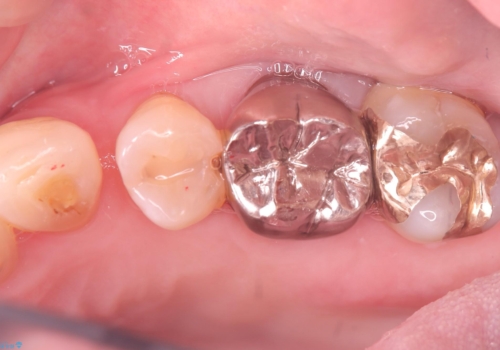

- 主訴:フロスを通したら、詰め物が取れた。適合の良いものを入れたい。

保険適用のメタルインレーが脱離しており、適合重視・咬合力が強いことからゴールドインレーでのやり替えとなりました。

フロスを通しインレーが脱離したことから、インレーと歯質との境に段差(適合不良)があった可能性があり、適合の良さや咬合力による補綴物の破折リスクを考慮し、ゴールドインレーでのやり替えとなりました。